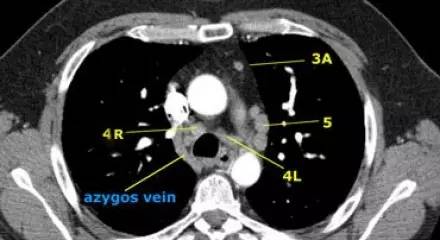

左下气管旁淋巴结(4L):图中所示上横线为主动脉弓上缘,下横线位于左肺上叶支气管上缘水平,穿过左主支气管。4L 淋巴结位于上下横线间的区域,包括所有位于肺动脉韧带内侧的气管旁淋巴结。 AP 区的主动脉弓下淋巴结(5)位于肺动脉韧带外侧。

肺动脉干上 CT 横断面的左下气管旁淋巴结(4L)、右下气管旁淋巴结(4R)、血管前淋巴结(3A)、主动脉弓下淋巴结(5) 、奇静脉(蓝字)。